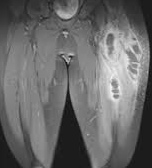

mit dem Spritzen von 3%-iger Kochsalzlösung unter die Haut

der Oberschenkel (Briefe aus Lambarene, S.575-576)